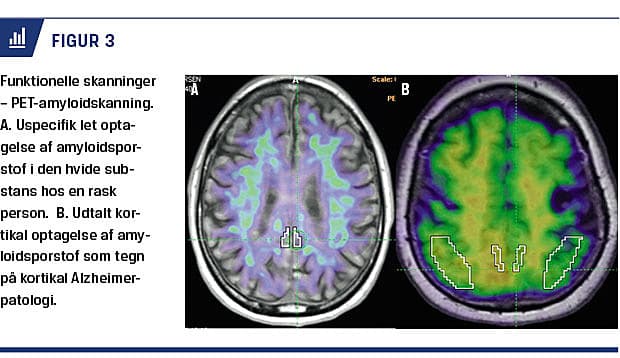

PET med anvendelse af sporstoffer, som bindes til AS-specifik patologi har vundet større udbredelse i de senere år. Fra 2008 har man anvendt PET med betaamyloidsporstoffet Pittsburgh compound B (PiB) i Danmark. Fordelen ved at påvise betaamyloid med PET frem for i CSV er, at PET oftest giver et enten-eller-signal (Figur 3), hvor betaamyloid i CSV kan variere som følge af prøvetagningsprocedurer og assay-variation. Der er dog ganske god overensstemmelse mellem de to metoder med ca. 85% konkordans [8]. PET-PiB synes umiddelbart at være CSV overlegen, når det gælder påvisning af betaamyloid [8], men især omkostninger og logistik begrænser anvendelsen. PET-amyloidskanning øger den diagnostiske sikkerhed og antallet af patienter, som får korrekt behandling, især hos personer med usikker diagnose [9-11]. Metoden kan således anbefales hos diagnostisk uafklarede patienter med kognitiv dysfunktion, hvor påvisning af AS-patologi får en afgørende betydning for information, rådgivning og behandling [12]. Man kan med stor sikkerhed afklare, om patienter har betaamyloid i hjernen ved en simpel visuel bedømmelse af PET-amyloidskanninger (sensitivitet og specificitet hhv. 98% og 89% [13]), men man skal være opmærksom på, at betaamyloidophobning i hjernen forekommer med stigende hyppighed med alderen hos kognitivt raske personer.